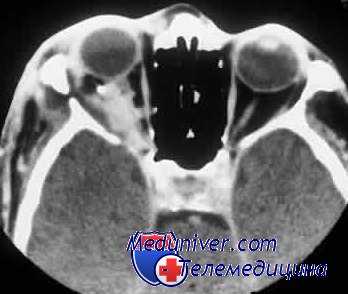

- Эндофтальмит. Инфекция поражает поверхность сетчатки. Даже когда глаз закрыт, чувствуются болезненные ощущения. Острота зрения стремительно снижается. При врачебном осмотре обнаруживаются характерные клинические проявления – расширенные сосуды конъюнктивы, позеленевшее или пожелтевшее глазное дно.